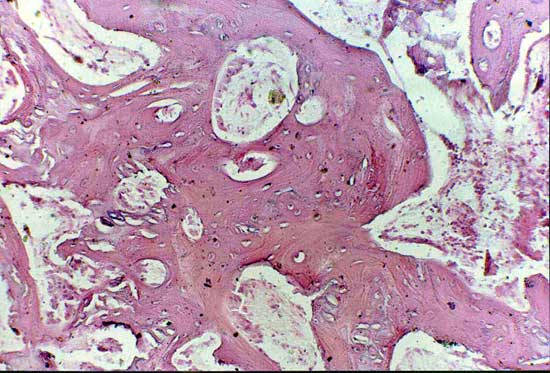

骨髓有核细胞100X                      骨髓有核细胞100X

2周软骨岛                              骨断端无骨痂

4周软骨钙化                            骨小梁形成

髓腔形成                              X线4周(BM vs MSC)